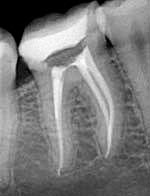

Рентгенологические снимки хорошо запломбированных корневых каналов.